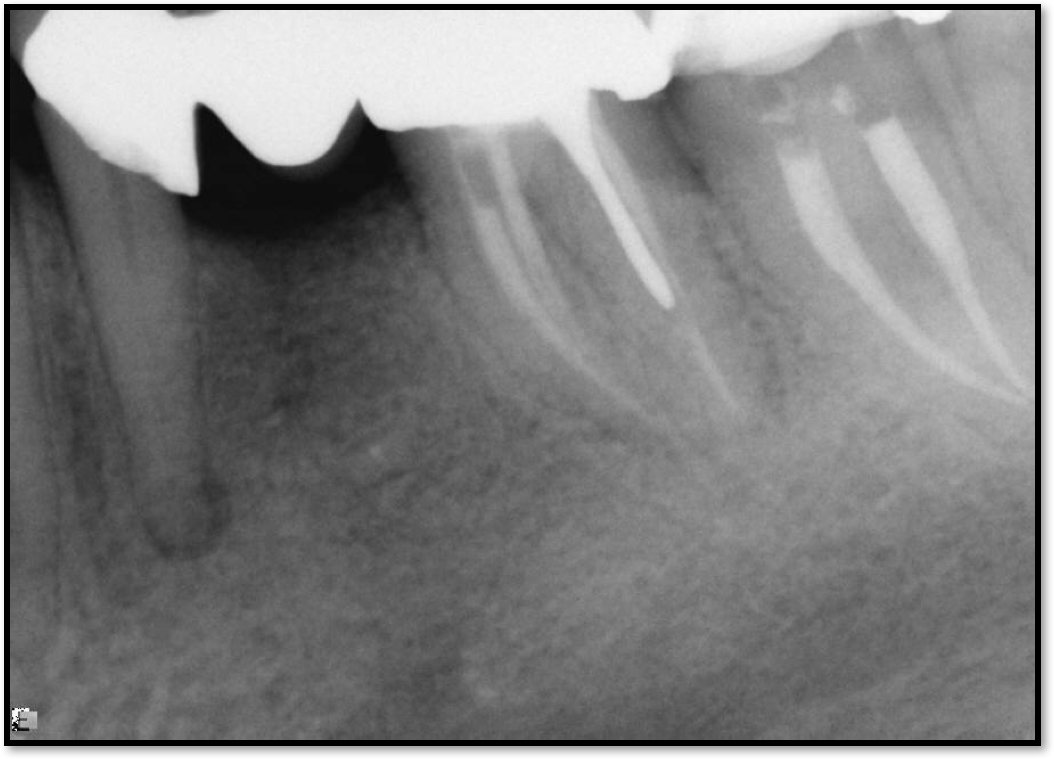

Occlusal Considerations

Occlusion is one of the most overlooked areas in endodontics; however, other than remaining structure, it is the most important factor.7 Patients who are heavy bruxers can cause the need for a root canal from the lateral forces. Patients who clench pose a different challenge with apical forces, yet the damage from both can be the same. Figure 7 shows a patient with bruxism. The patient had pain in response to hot and cold stimulus, and the clinicians needed a bitewing to determine which tooth was causing the pain. From the periapical (PA), it was clear that tooth No. 2 had a large problem, No. 3 had a crown, and No. 4 had a large restoration. Any of the three may have been the source of the problem.

With the bitewing shown in Figure 8, it became clear there was gross decay in tooth No. 3 that could not be seen on the PA, and there was a periodontal defect, a pulp stone, in No. 2. There was also a class V lesion revealing the bruxism, flat occlusion, multiple restorations in No. 30, a post in No. 31, and decay on No. 2 as well. The post in No. 31 was useless because when a post is placed, it must be the right length, width, and size. If the post is too short, there will be a greater fulcrum and the tooth will break. If it is too long, the clinician can break it by wedging it. If it is too short, it will not hurt the tooth, but it will not provide any valuable function. It is overall preferable to do posts in teeth having just single restorations rather than abutments for bridges because those teeth are already under greater force. If the technique is not performed correctly, iatrogenic issues may result.

Fig 7. Bruxism.

Figure 7

Fig 8. Bitewing revealed decay and other problems.

Figure 8